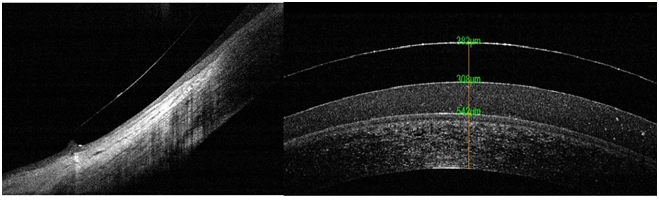

Correct support in bulbar conjunctiva and good lacrimal reservoir (Figure 8).

Figure 8 OCT image of lens support in conjunctiva, and cut where we observed the lacrimal reservoir between cornea and lens.

As a key point in the adaptation, it is to indicate that the semi-scleral or scleral lenses must have a total diameter capable of supporting the total weight of the lens in the anterior ocular surface and form a sufficient tear reservoir. Although talking about these lenses as contact lenses would be questionable, since there is no corneal contact, there is peripheral contact at the conjunctival level. Since no surveyor provides information on this contact area, extensive analysis by slit lamp and OCT image support is of great importance. When the cornea is isolated in a lacrimal reservoir, it is of great importance to monitor the quality of the tear to control the hours of use and indicate a correct maintenance system